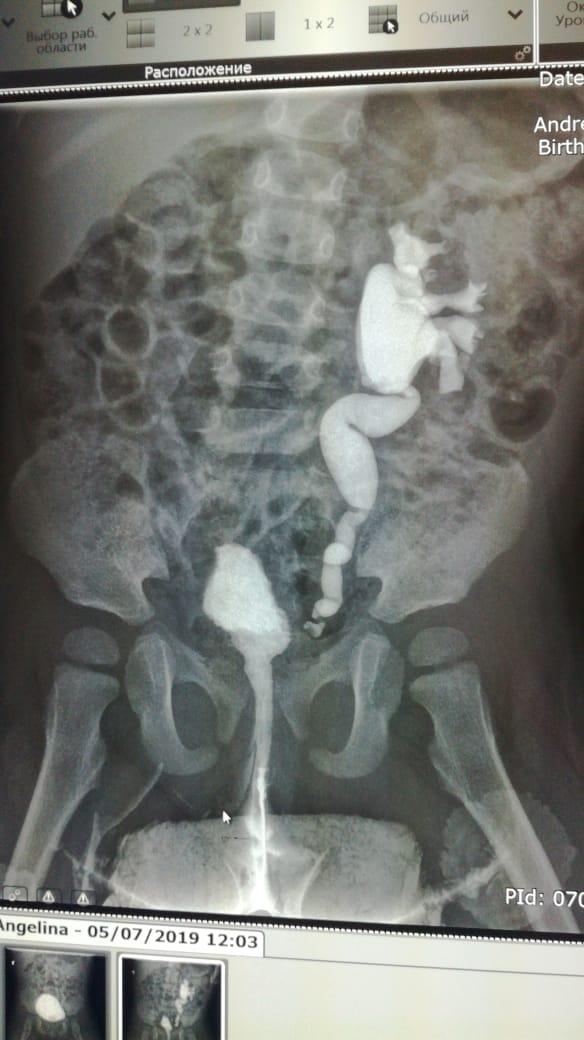

Здравствуйте.Ребенку 14.09.17г.р.сделали эндоскопическую коррекцию ПМР 4ст.второй раз ,хотя квота выписывалсь на сложную операцию.После коррекции ребенок стал мочиться еще реже и ухудшился ОАМ на четвертые сутки.